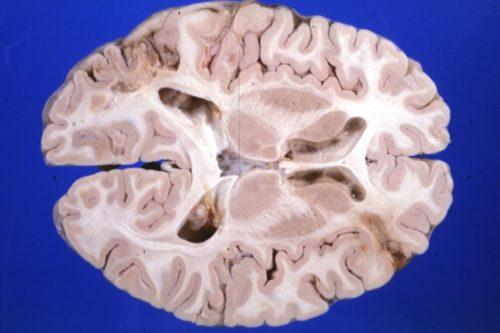

По заболеваемости инсульт составляет 0,3%, а показатель смертности от него – четверть от общей для всего населения РФ. Высок также процент инвалидизации (около 80%), включая стойкую утрату трудоспособности, навыков самообслуживания. Инсульт как острое поражение сосудов головного мозга подразделяется на два основных типа: геморрагический и ишемический.

Первый представляет собой кровоизлияние в мозг из-за разрыва сосуда. Второй развивается в результате непроходимости артерий и, соответственно, продолжительной ишемии с отмиранием участка тканей (инфаркт мозга). Симптоматика обеих разновидностей схожа, однако различается динамикой проявления – при ишемическом она развивается медленнее. Характерны тошнота, рвота, головная боль, нарушения сознания. По характеру симптомов, как и в случае аневризмы, можно судить о локализации очага поражения.